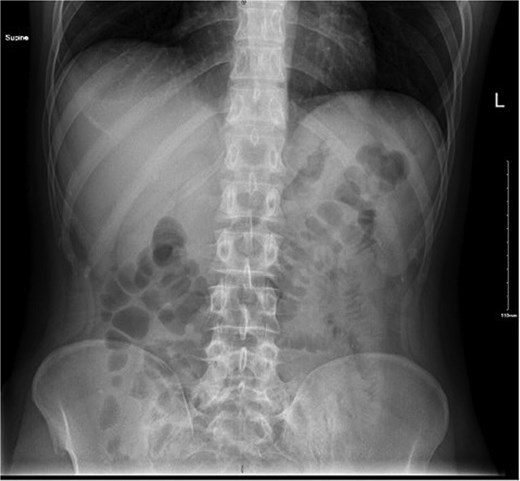

This is a case of a 29-year-old male with no past medical history and a surgical history of open inguinal hernia repair fourteen years ago, who presented to the emergency department complaining of severe abdominal pain for one day. The pain was localized at the lower abdomen, more in the right lower quadrant, and gradually worsened after the patient had eaten his dinner containing poultry. His symptoms were associated with nausea and vomiting, with normal bowel motion. The patient denied fever, hematemesis, melena, or hematochezia. Upon examination, the patient appeared in mild distress due to pain with the following vital signs: temperature: 36.7°C; pulse rate: 96/min; respiratory rate: 19/min; and blood pressure: 138/72 mmHg. The abdominal examination revealed distension, tenderness at the right iliac fossa with signs of muscle guarding and rebound tenderness, and an empty rectum on rectal examination. The laboratory workup results were unremarkable apart from leukocytosis at 13.90 × 109/l. An abdominal X-ray revealed no signs of pneumoperitoneum (Fig. 1).